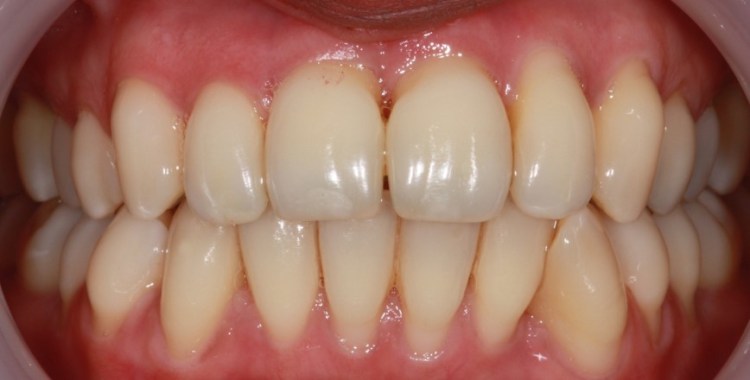

Non-surgical treatment

Initially gum disease is managed with oral hygiene advice to optimise self-performed plaque control. Non-surgical periodontal treatment “deeper cleaning” is carried out to disrupt the biofilm and remove hard calculus deposits from the root surfaces. Sometimes antibiotics are prescribed alongside this treatment if it is deemed particularly aggressive.